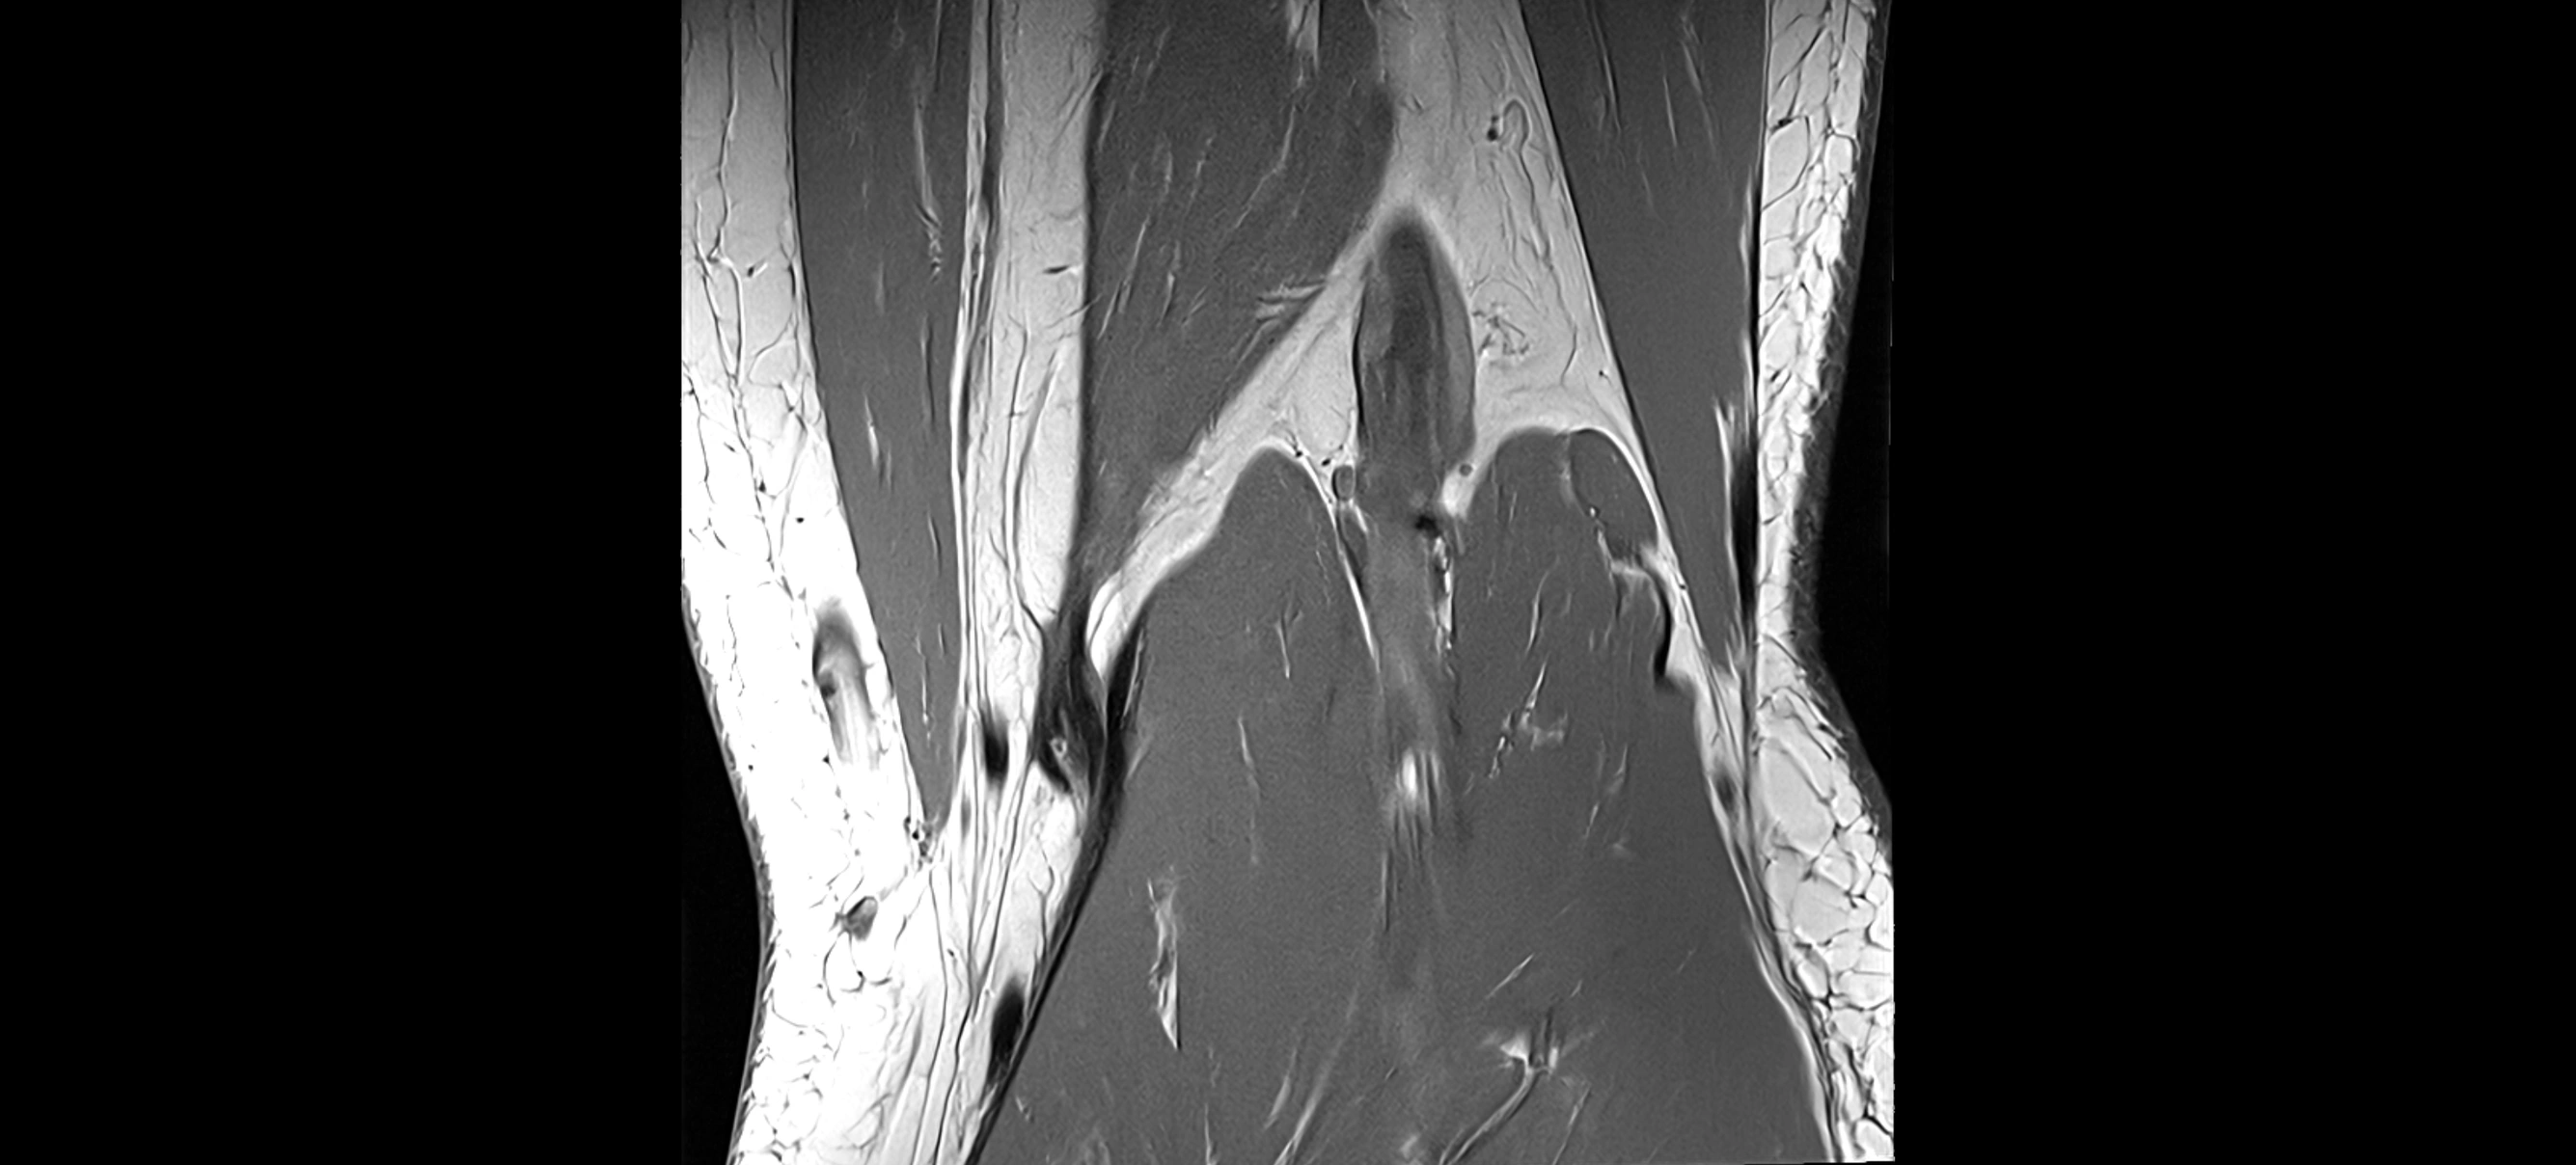

MRI images

image